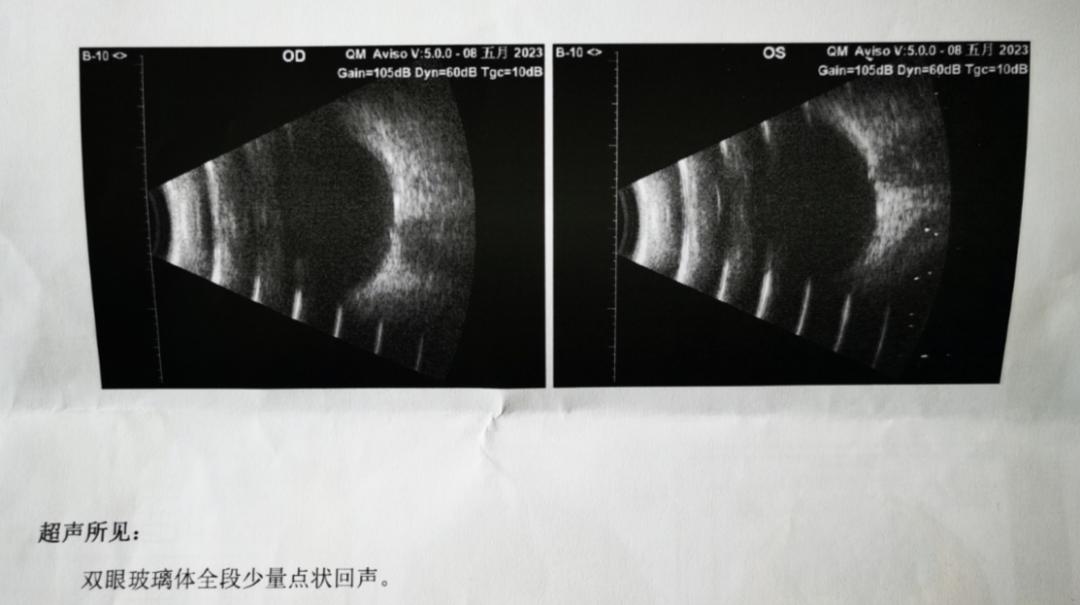

▲飞蚊症患者眼部b超图。即使是少量、细小的浑浊物,投在视网膜上也有可能形成巨大的“飞蚊”/图源:赵睿佳